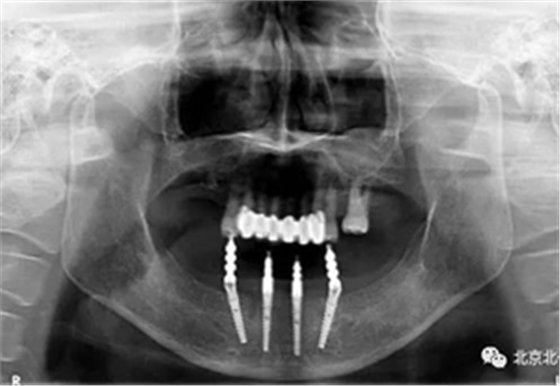

圖十五:術(shù)后即刻拍X片

圖十七:拍X片確認無誤差

圖二十一:半年后復(fù)查X片

圖二十二:2015年到2016年復(fù)查時X片 ,有圖有真相

沒有假貨,貨真價實,完成三年復(fù)查。